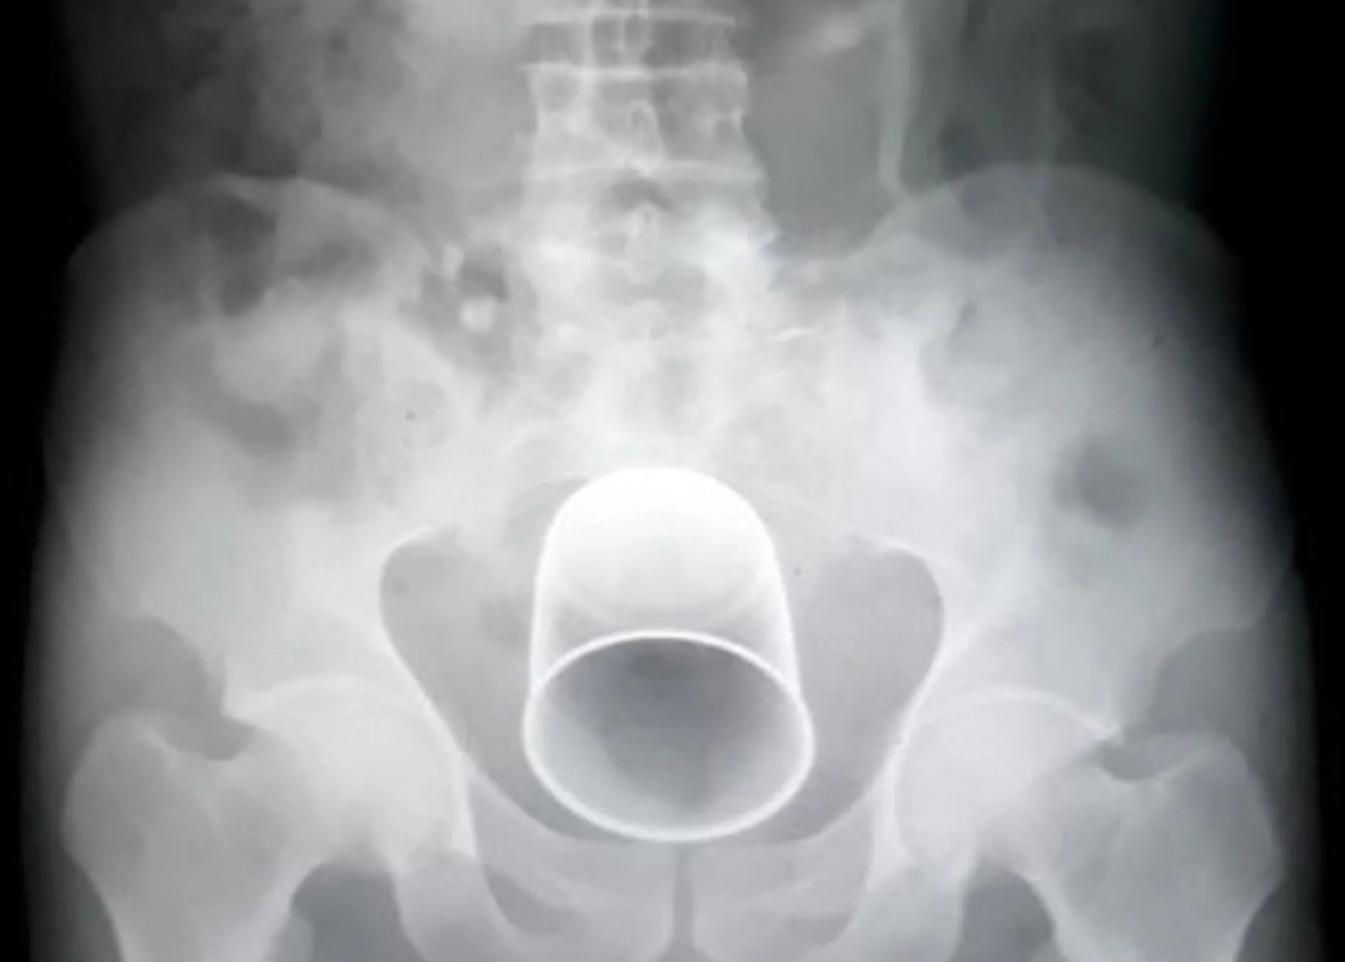

Врач предупредил об опасности введения бытовых предметов в прямую кишку Аноним 28/01/26 Срд 09:03:39 19129725

Колопроктолог Даниэль Броско призвал не вводить бытовые предметы в прямую кишку, поскольку такая сексуальная практика опасна для здоровья. Его слова передает издание Terra.

Броско предупредил, что из-за инородных тел в анусе может возникнуть перфорация кишечника.

В таком случае хирургическое вмешательство неизбежно, подчеркнул он.

В худшем случае все может закончиться смертью, как это случилось с одним из пациентов доктора, а в лучшем — установкой колостомического мешка

. «Поскольку вам придется перенести операцию, вам потребуется колостомия, другого выхода нет, и восстановить кишечник после этого очень сложно. Поэтому это крайне серьезное, очень тяжелое дело», — отметил врач.

Если бытовой предмет все-таки застрял в прямой кишке, врач призвал не принимать слабительные средства. Вместо этого следует сразу же обратиться в больницу. Тем же, кто хочет исследовать свое тело, посоветовал использовать исключительно секс-игрушки.